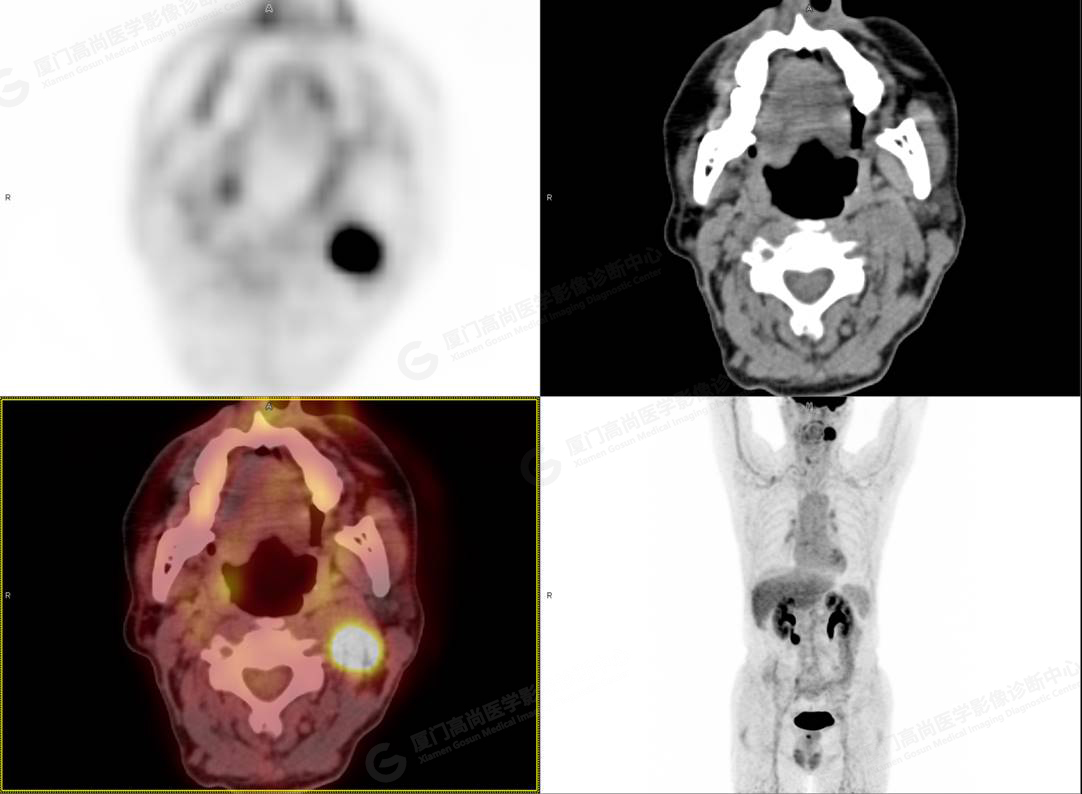

PET/CT影像圖

圖2

PET/CT所見:左側頸部(II區(qū))見腫大淋巴結,大小約2.5cm×2.3cm,其內密度不均,邊界尚清,放射性攝取異常增高,早期SUVmax 11.5,延時SUVmax 14.5。

影像診斷: 左側頸部(II區(qū))腫大淋巴結,代謝異常增高,考慮腫瘤性病變可能性大(淋巴瘤?轉移瘤?),建議病理學檢查明確。

病理診斷:(左頸部結節(jié))副神經節(jié)瘤。